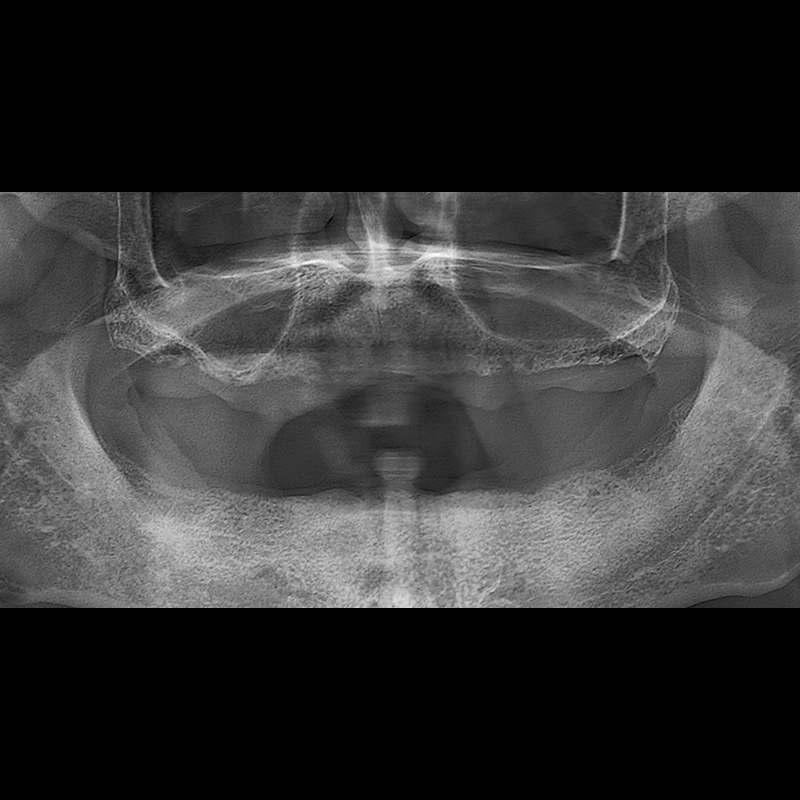

BEFORE AFTER

种植牙前后的照片 2025.05.30

在缺失的牙齿部分和难以挽救的牙齿位置植入了种植牙。